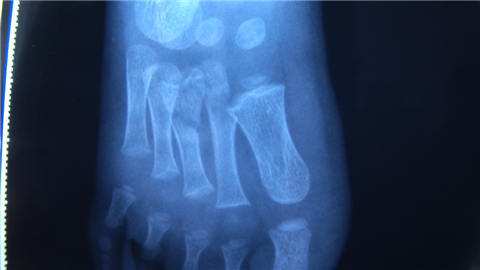

孩子被送到医院后检查显示,右脚的第二个脚趾头跟第三个脚趾头骨折,脚面大部分皮肤坏死了。